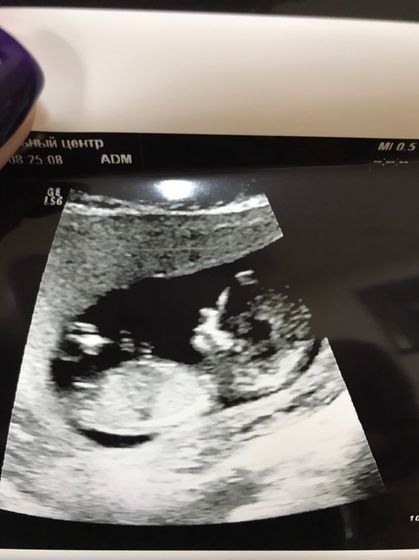

Вот и сходили мы на первый скрининг))увидела крошечку??спал ещё, врач немножечко растолкал и он показал нам свои ручки, пальчики))так круто!!! предположиьельно мальчик будет, говорит доктор «вроде что-то ростки между ног, но плохо видно»))))а я и не сомневалась, так и знала, что пацан??

Такой сладенький, растите здоровенькими ??

А по профилю можно уже определить на кого похож!!! У нас такое же первое фото было.И ясно стало что папин сын?